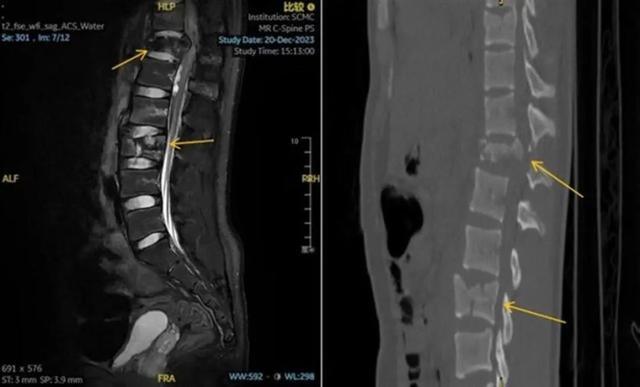

术前 CT 显示,孟迪的胸、腰椎多发爆裂性骨折伴移位(图源:上海儿童医学中心)